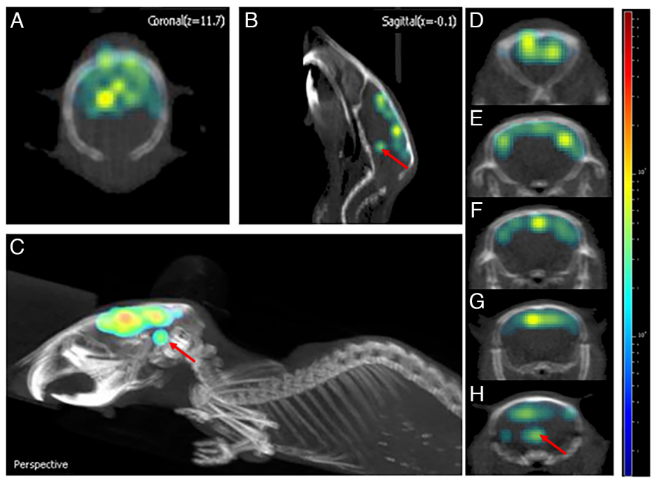

在小鼠的3D腦成像研究中,作者發(fā)現(xiàn)信號(hào)可達(dá)小鼠腦部深層0.5 cm處(圖4)。并且,對(duì)比野生型和AD小鼠不同位置的3D腦成像信號(hào)強(qiáng)度均有不同,差別可達(dá)2.72倍,相較于二維腦成像的信號(hào)差別(1.8倍)有所增加。所以,該方法不僅可以區(qū)分健康和AD小鼠,同時(shí)也提高了定量分析結(jié)果(圖5)。

圖4. ADLumin-5探針的三維腦成像。圖片來源:PNAS